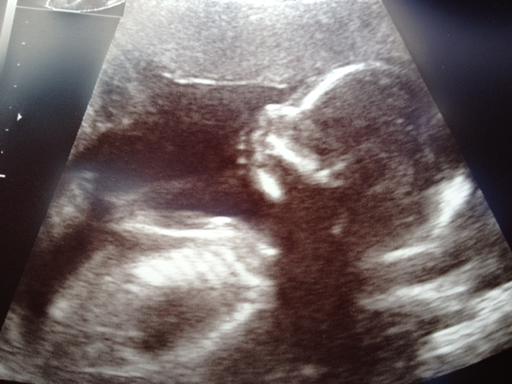

Bebben visar upp sig*

En liten skrutt som var frisk och kry gömde sig därinne;)

Och precis som storasyster ville h*n inte visa upp sig lr bli fotad så de blev inga toppen bilder men man är ju glad bara allt är bra:))